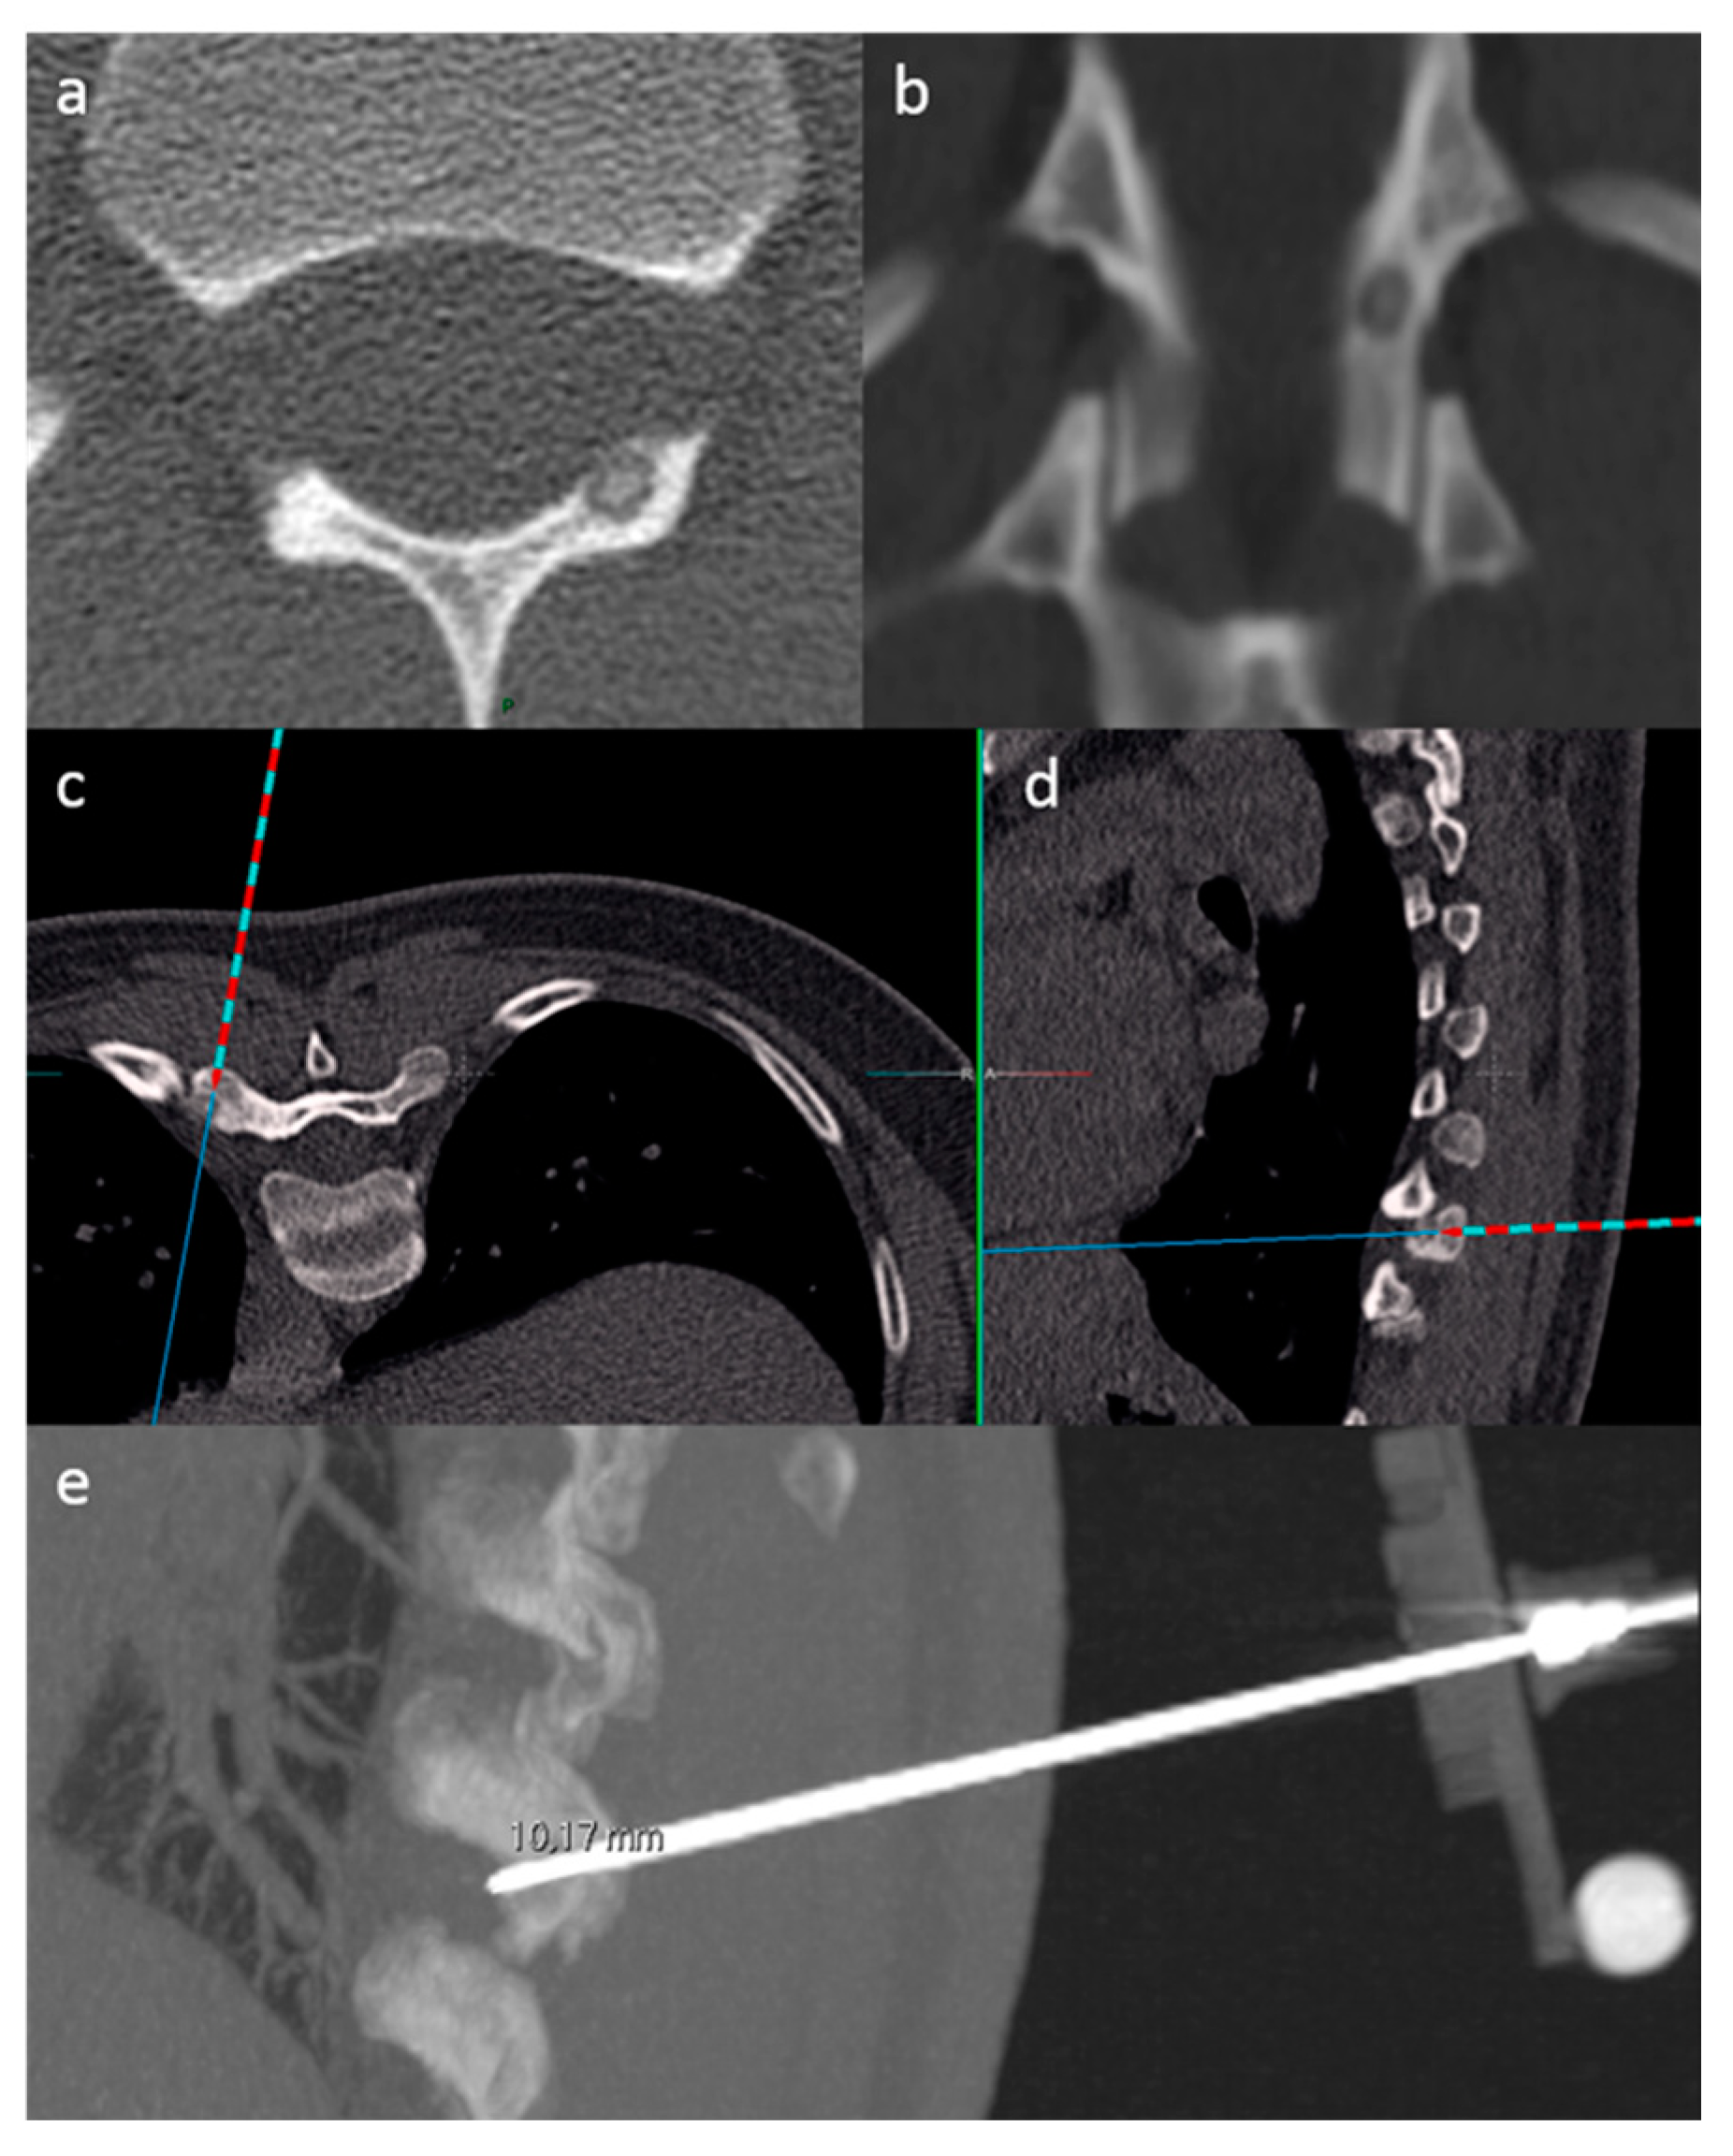

2.2.1. Biopsies

2.3. SIRIO Augmented Reality Navigation System